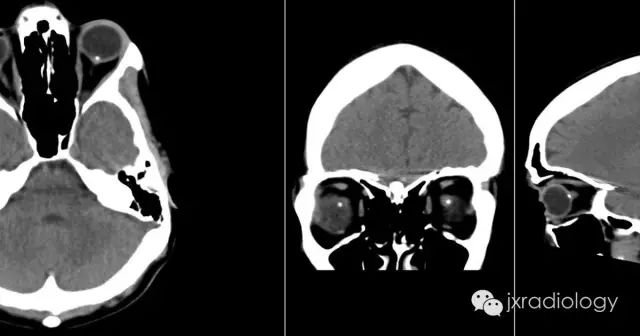

视乳头玻璃膜疣(Optic disc drusen,ODD)也称为透明小体或玻璃膜疣,是相对常见的病变。它们通常在CT或异常眼底镜检查的随访中偶然发现。

CT上的征象反映出玻璃膜疣含钙增多。

病例图片:

CT:虽然在儿童时期就能被识别出来,但它们很小,而且没有矿化。因此,在儿科病人中很少发现,尽管在薄层扫描中,密度和肿胀的区域可能很明显。

2.5视盘玻璃膜疣 视盘玻璃膜疣(optic disc drusen,ODD)是一种与视网膜玻璃膜疣名称相同而病理改变及发病机制迥异的疾病,其可分为原发性和继发性两种,后者继发于炎症和外伤。在此所述为与先天有关的原发性视盘玻璃膜疣。其发病机制有研究认为可能是基因突变引起;另有研究认为是因视神经纤维轴浆崩解、钙化或先天性的血管异常造成的血浆蛋白传输障碍郁积在视盘引起。电子显微镜下见玻璃膜疣多位于视盘筛板前区、视盘内有大小不一、呈环板状排列的无细胞结构的嗜碱性小体[2]。根据玻璃膜疣病变位置的深浅有可分为埋藏性玻璃膜疣和表面性玻璃膜疣。表面性玻璃膜疣眼底检查可见视盘结节状胶样隆起,并可融合为不规则的较大团块向玻璃体内突出如桑葚状,较易诊断。埋藏性ODD的眼底影像学表现显示视乳头轻度隆起,边界欠清晰,有时显示假性视乳头水肿。因疣体压迫、损伤视乳头上或周围毛细血管,可引起视盘或其周围视网膜出血。自发荧光表现为视盘自发荧光。FFA对诊断埋藏性玻璃膜疣具有极其重要的价值,造影早期视盘局部荧光素明显增强,造影后期玻璃膜疣处荧光素染色明显,但无荧光素渗漏。OCT检查可见患眼视盘视网膜神经纤维层(RNFL)高度隆起,其下方可见团块状高反射信号。B超是诊断ODD最有效的方法,因疣内存在钙质,检测结果会显示有强回声光团存在于视盘强方,其周边显示呈暗区,降低增益,光团不消失。有研究[18]发现对埋藏性视盘玻璃膜疣使用B超联合OCT检查,是非常可靠的诊断方法,两者联合应用,可有效提高检出率。有学者[19]认为,将玻璃膜与视网膜色素上皮层之间的drusen定义为玻璃膜疣,而将发生在视盘的drusen定义为视盘玻璃疣,这样可以更加明确drusen的概念。3 总结